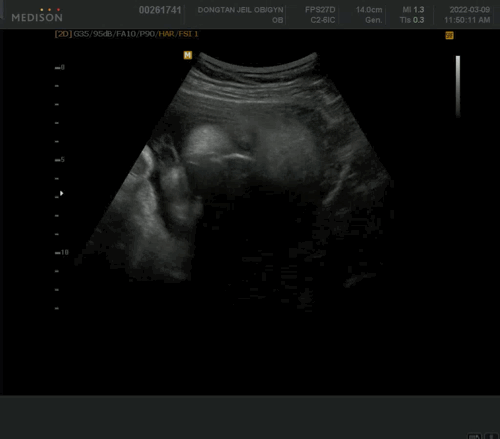

그 다음엔 초음파.

주수에 비해 좀 작긴 하지만 정상 범위 안에 있단다.

오늘은 기특하게도 얼굴도 잘 보여주고

(형아와서 반가웠니??) 양수 냠냠 모습도 보여줌. 싱기방기

촘파 보는데 잘 움직이니 피식하며 잘 움직이네- 라고 혼잣말 하셨는데 왠지 애정이 느껴졌다. ㅎ